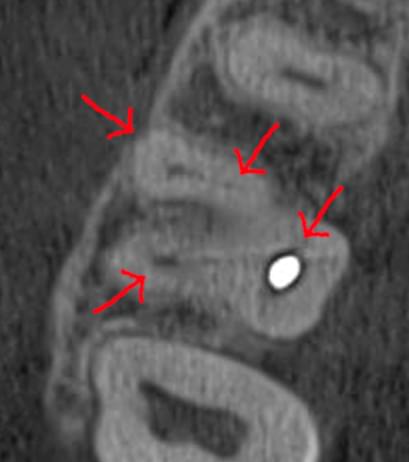

Часто причиною зубного болю є гайморит, і навпаки — причиною запалення пазух є хворий зуб. На звичайному знімку пазуха виглядає як темна пляма. На КТ ми бачимо стан слизової, наявність кіст або сторонніх тіл (наприклад, залишків пломбувального матеріалу), що критично важливо для правильного діагнозу.